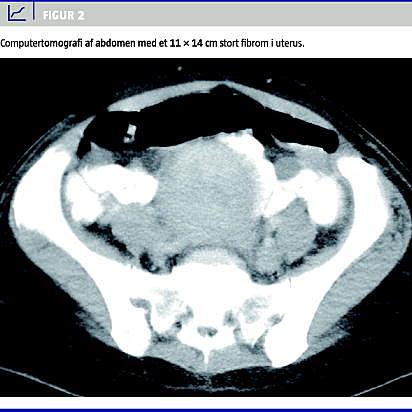

Ved CT af abdomen genfandt man en 11 14 cm stor ensartet proces i uterus (Figur 2 ), minimal ascites samt hyperekkogene processer i leveren, der initialt blev beskrevet som metastasesuspekte, men senere tolkedes som hæmangiomer. Leukocytskintigrafi var uden sikre opladninger. Da patienten fortsat var diagnostisk uafklaret, bestiltes helkropspositronemissionstomografi (PET).

Patogenesen formodes bl.a. at være irritation af peritoneum pga. tumor og væskesekretion, der er forårsaget af nye kardannelser, der breder sig fra abdomen til pleura, især på højre side [1, 3-5]. Især større tumorer (> 10 cm) har tendens til at fremkalde syndromet [5].